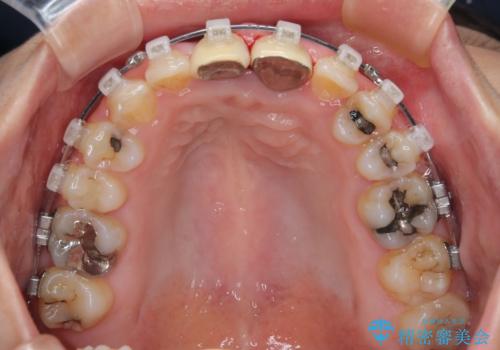

- クリアブラケット

マウスピース装着は煩わしいとのことで、表側のワイヤー装置にて矯正治療を行うこととしました。

前歯のクラウンは、歯肉内深くに削り込まれており、歯肉の炎症が継続していたため、矯正治療後に歯周外科処置を行い、歯肉の腫れを改善させました。